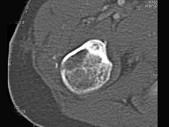

问题 男,28岁,右上肢疼痛,夜间加重,服用止痛药可缓解,结合图像,最可能的诊断是?(?)

选项 A.骨瘤 B.骨软骨瘤 C.骨样骨瘤 D.骨囊肿 E.成骨细胞瘤

答案 C